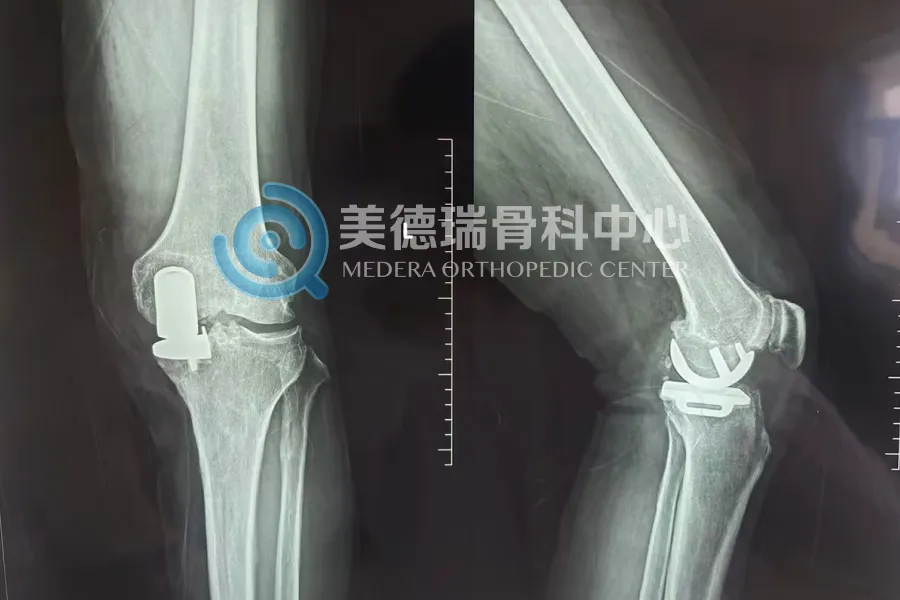

在关节外科领域,从50岁患者的股骨头坏死全髋关节置换,到80岁以上高龄患者重度膝骨关节炎的膝关节置换手术,美德瑞专家团队及美德瑞骨科中心展现了成熟的围手术期管理能力和规范的临床路径。单髁置换术(UKA),则充分体现了集团量体裁衣的精准诊疗方案,通过综合考虑患者膝关节的病变程度及整体健康状况,通过更小的创伤解决老年患者的膝关节局限性磨损问题,快速康复提高生活质量。